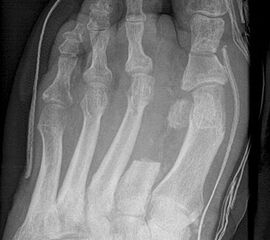

Eitrig-infiziertes Ulkus an der Spitze der 2. Zehe als Indikation zur Endgliedamputation.

Abbildung 13

Chronisches Ulkus mit Infektion (Abb. 13).